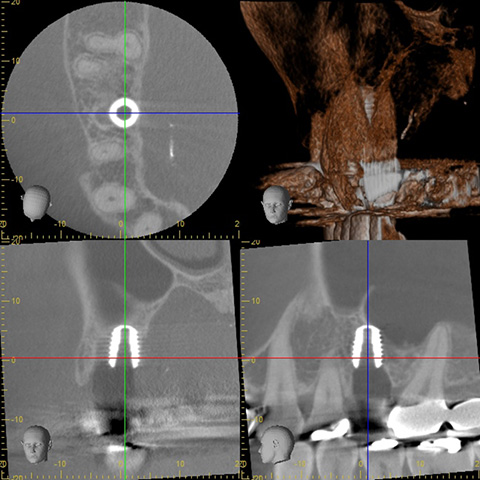

オペ前のCT写真です。

完全に割れている歯を抜いて、インプラント治療を行います。

オペ後のCT写真です。